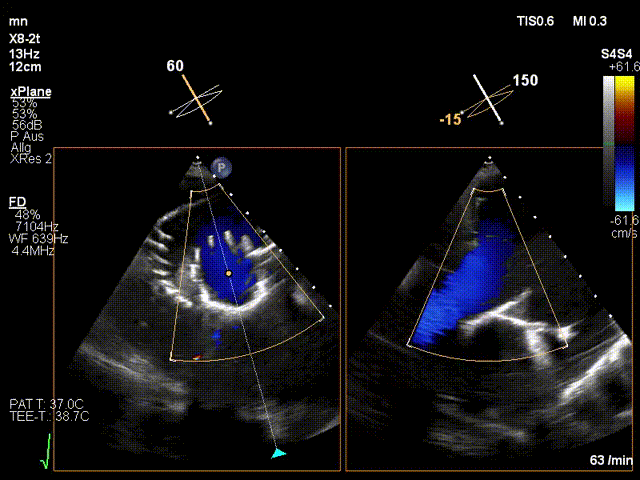

手術(shù)在全麻狀態(tài)下進(jìn)行。在加拿大圣保羅醫(yī)院的Anson Cheung教授的指導(dǎo)參與下,術(shù)者采用經(jīng)右側(cè)頸靜脈入路的方式將輸送器送入患者心臟內(nèi),在TEE及DSA引導(dǎo)下調(diào)整輸送器頭端角度,使得輸送器與三尖瓣瓣環(huán)平面垂直。在輸送器進(jìn)入右心室后釋放室間隔錨定裝置,而后釋放瓣葉夾持件(2個(gè)耳片結(jié)構(gòu))成垂直狀態(tài)。在TEE及DSA確定夾持件固定至三尖瓣葉根部且位于右室側(cè)后釋放人工瓣心房側(cè)盤片。隨后調(diào)整瓣膜同軸性以及室間隔錨定件位置(貼合室間隔),前推藏針管并固定,進(jìn)而釋放室間隔錨定裝置,并再次確認(rèn)瓣膜位置、穩(wěn)定性及同軸性,合攏輸送鞘后撤出輸送器,完成LuX-Valve Plus人工三尖瓣瓣膜的植入。

LuX-Valve Plus經(jīng)血管三尖瓣置換系統(tǒng)本次“出海”圓滿完成,術(shù)后Jörg Hausleiter教授對(duì)LuX-Valve Plus經(jīng)血管三尖瓣置換系統(tǒng)的器械性能和治療效果大為稱贊,認(rèn)為L(zhǎng)uX-Valve Plus的手術(shù)體驗(yàn)非常好。術(shù)后即刻超聲顯示三尖瓣反流消失,血流動(dòng)力學(xué)改善顯著,患者恢復(fù)快。Anson Cheung教授也肯定了LuX-Valve Plus術(shù)中操作的便捷性,認(rèn)為L(zhǎng)uX-Valve Plus容錯(cuò)率高,對(duì)術(shù)中影像的依賴較小,后期希望可以更多的應(yīng)用LuX-Valve Plus三尖瓣置換系統(tǒng)于臨床實(shí)踐,讓更多的三尖瓣重度反流患者盡早獲益,改善預(yù)后。